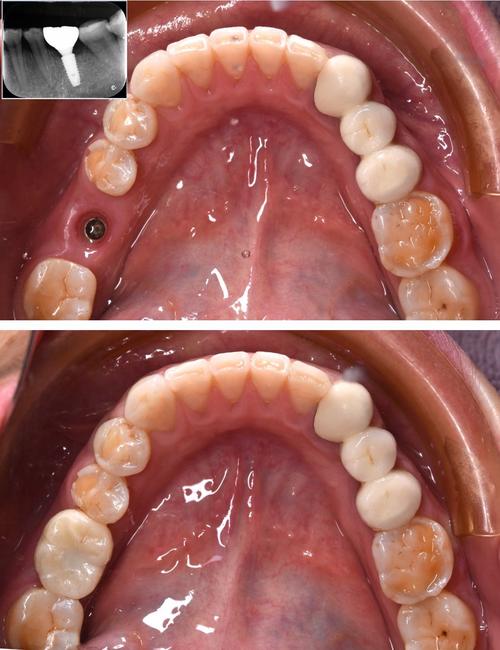

这是目前应用最广泛的微创技术,通过术前CBCT(锥形束CT)扫描、口内数据采集,结合3D打印技术制作个性化种植导板,导板能预先设计种植体的植入位置、角度、深度,术中医生只需沿着导板的引导孔操作,即可精准将种植体植入理想位置。

- 优势:切口通常仅需3-5mm(约米粒大小),无需翻开牙龈全层,避免损伤神经、血管;手术时间短(单颗牙约30分钟),术后肿胀、疼痛轻,恢复快(一般3-5天即可正常生活)。

- 适用情况:骨量充足(牙槽骨高度、宽度足够)、无严重炎症的简单缺牙病例,如单颗牙缺失、多颗牙缺失且骨条件良好者。

即刻种植与即刻负重

即刻种植指拔牙后立即在新鲜拔牙窝内植入种植体,减少手术次数;即刻负重则是在种植体植入后,同期安装临时牙冠,实现“即种即用”。

- 微创结合:这两种技术常与数字化导板联合,利用微创切口植入种植体,减少手术创伤,前牙区拔牙后,若牙槽骨条件允许,通过即刻种植可避免拔牙后3-6个月的等待,且微创操作能最大限度保留牙龈形态,美观效果更佳。